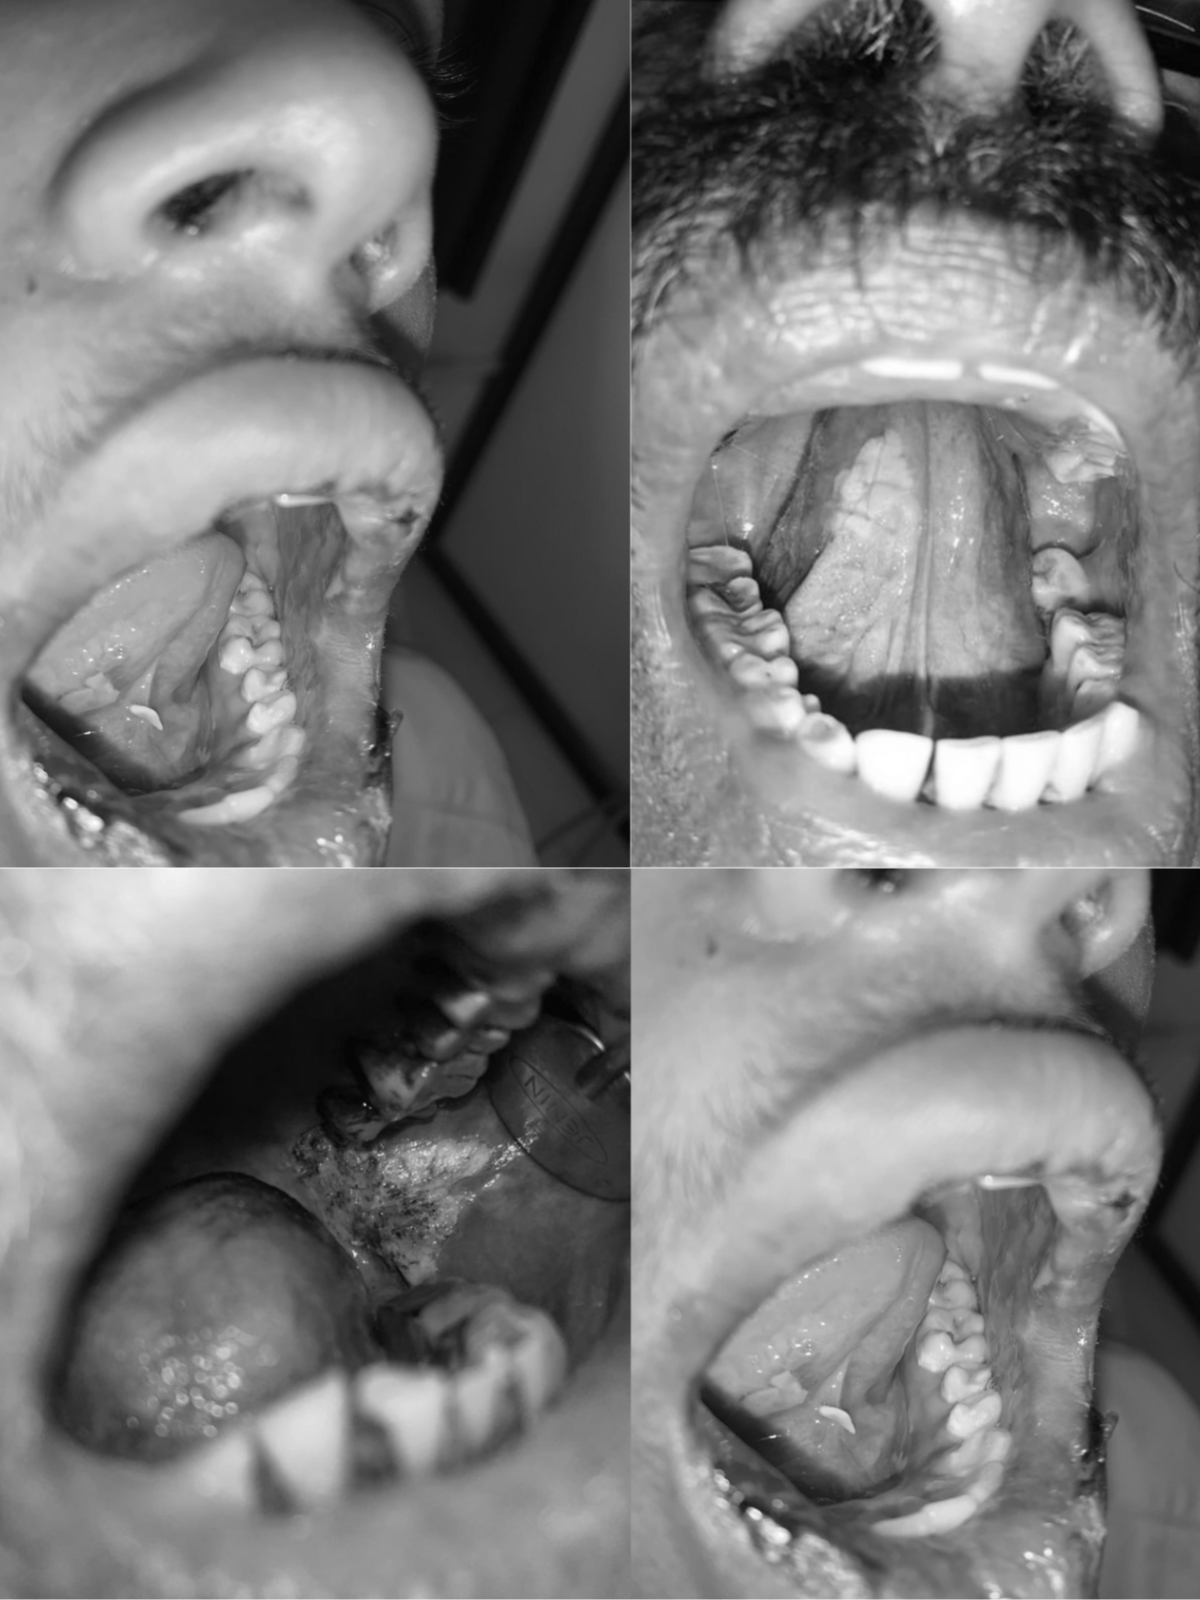

- Diagnosis & management of oral ulcers, white patches, burning mouth syndrome, and precancerous conditions

Our Work Speaks for Us

Discover our exceptional work, showcasing precision, expertise, and transformative results in oral, maxillofacial, and aesthetic procedures.